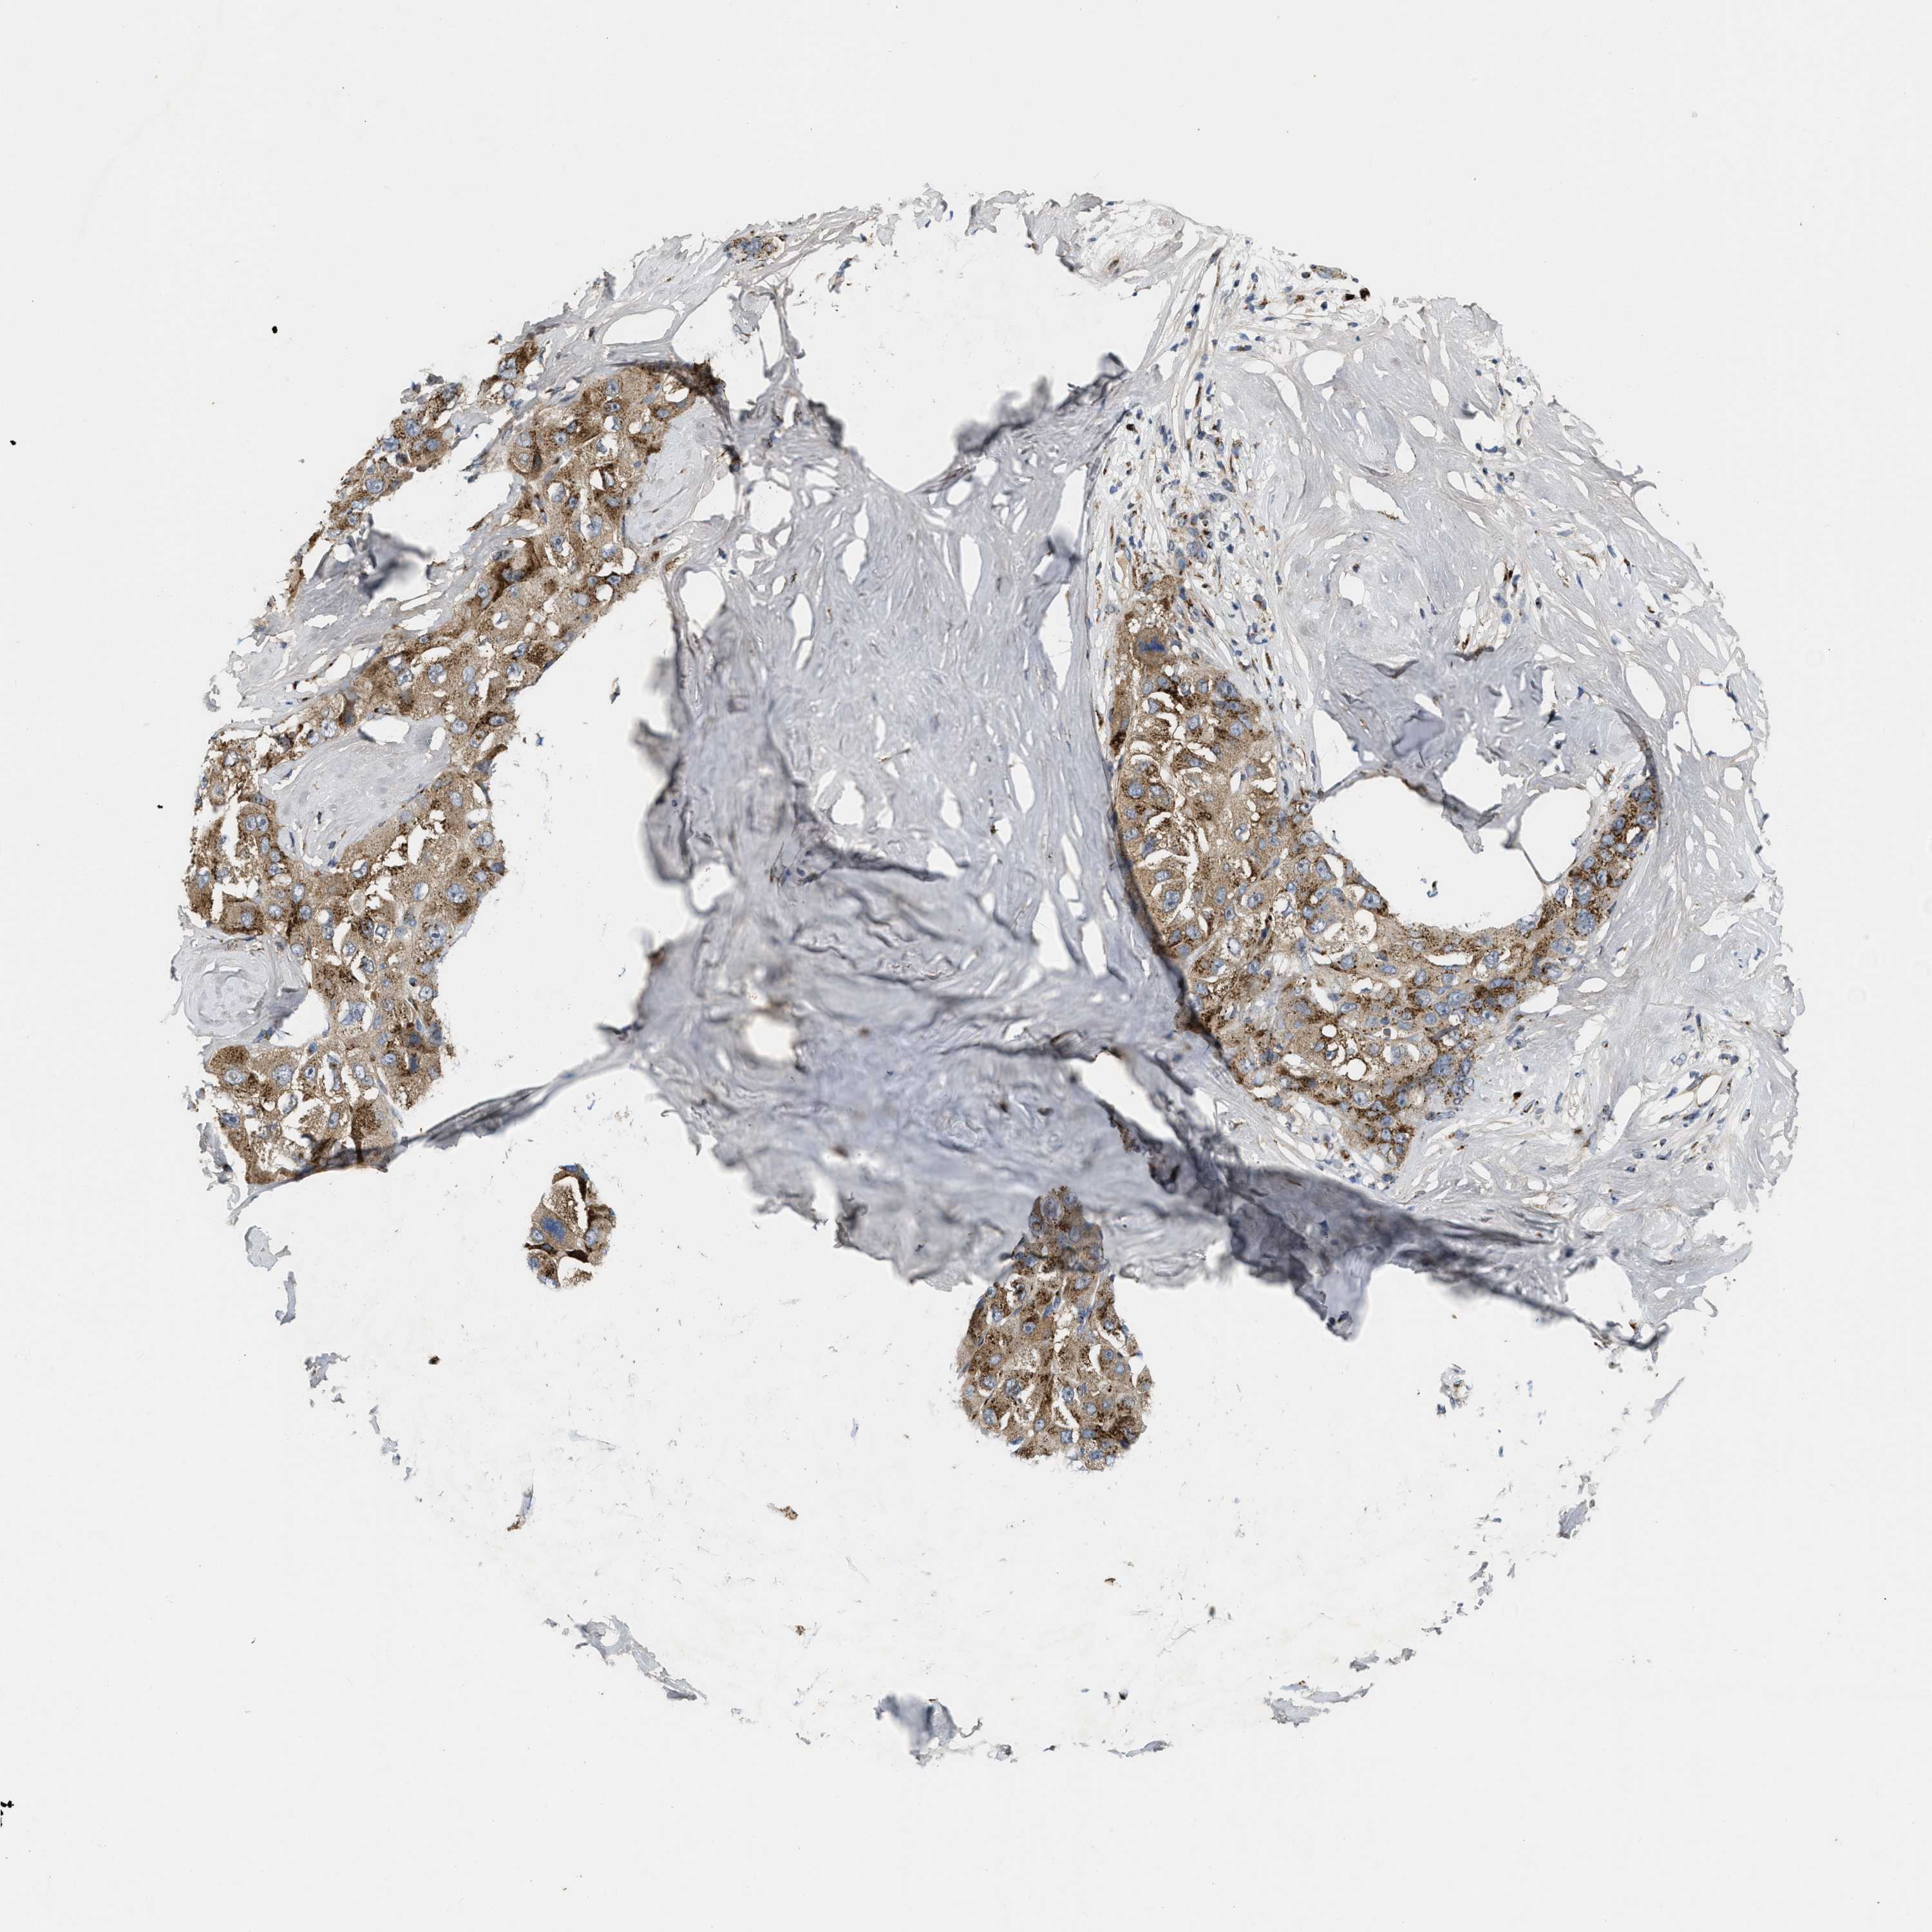

LIVER CANCER - Protein expressioni

A mouse-over function shows sample information and annotation data. Click on an image to view it in a full screen mode. Samples can be filtered based on level of antibody staining by selecting one or several of the following categories: high, medium, low and not detected. The assay and annotation is described here.

Note that samples used for immunohistochemistry by the Human Protein Atlas do not correspond to samples in the TCGA dataset.

Antibody stainingi

Antibody staining in the annotated cell types in the current human tissue is reported as not detected, low, medium, or high, based on conventional immunohistochemistry profiling in selected tissues. This score is based on the combination of the staining intensity and fraction of stained cells.

Each image is clickable and will lead to virtual microscopy that enables deeper exploration of all samples and also displays staining intensity scores, fraction scores and subcellular localization as well as patient and tissue information for each sample.

Antibody HPA018821

Staining

High

Medium

Low

Not detected

Intensity

Strong

Moderate

Weak

Negative

Quantity

>75%

75%-25%

<25%

None

Location

Nuclear

Cytoplasmic/membranous

Cytoplasmic/membranous,nuclear

Cholangiocarcinoma

Carcinoma, Hepatocellular, NOS